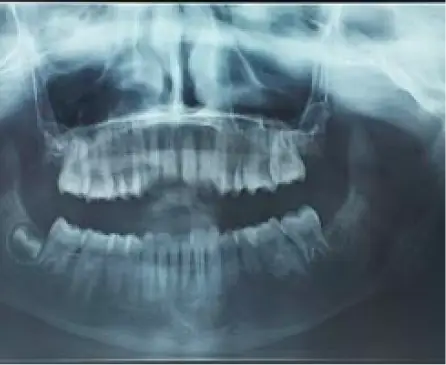

Panoramic radiograph revealing a well defined radiolucency in the left mandibular body and anterior ramus region, causing root resorption of the involved teeth.